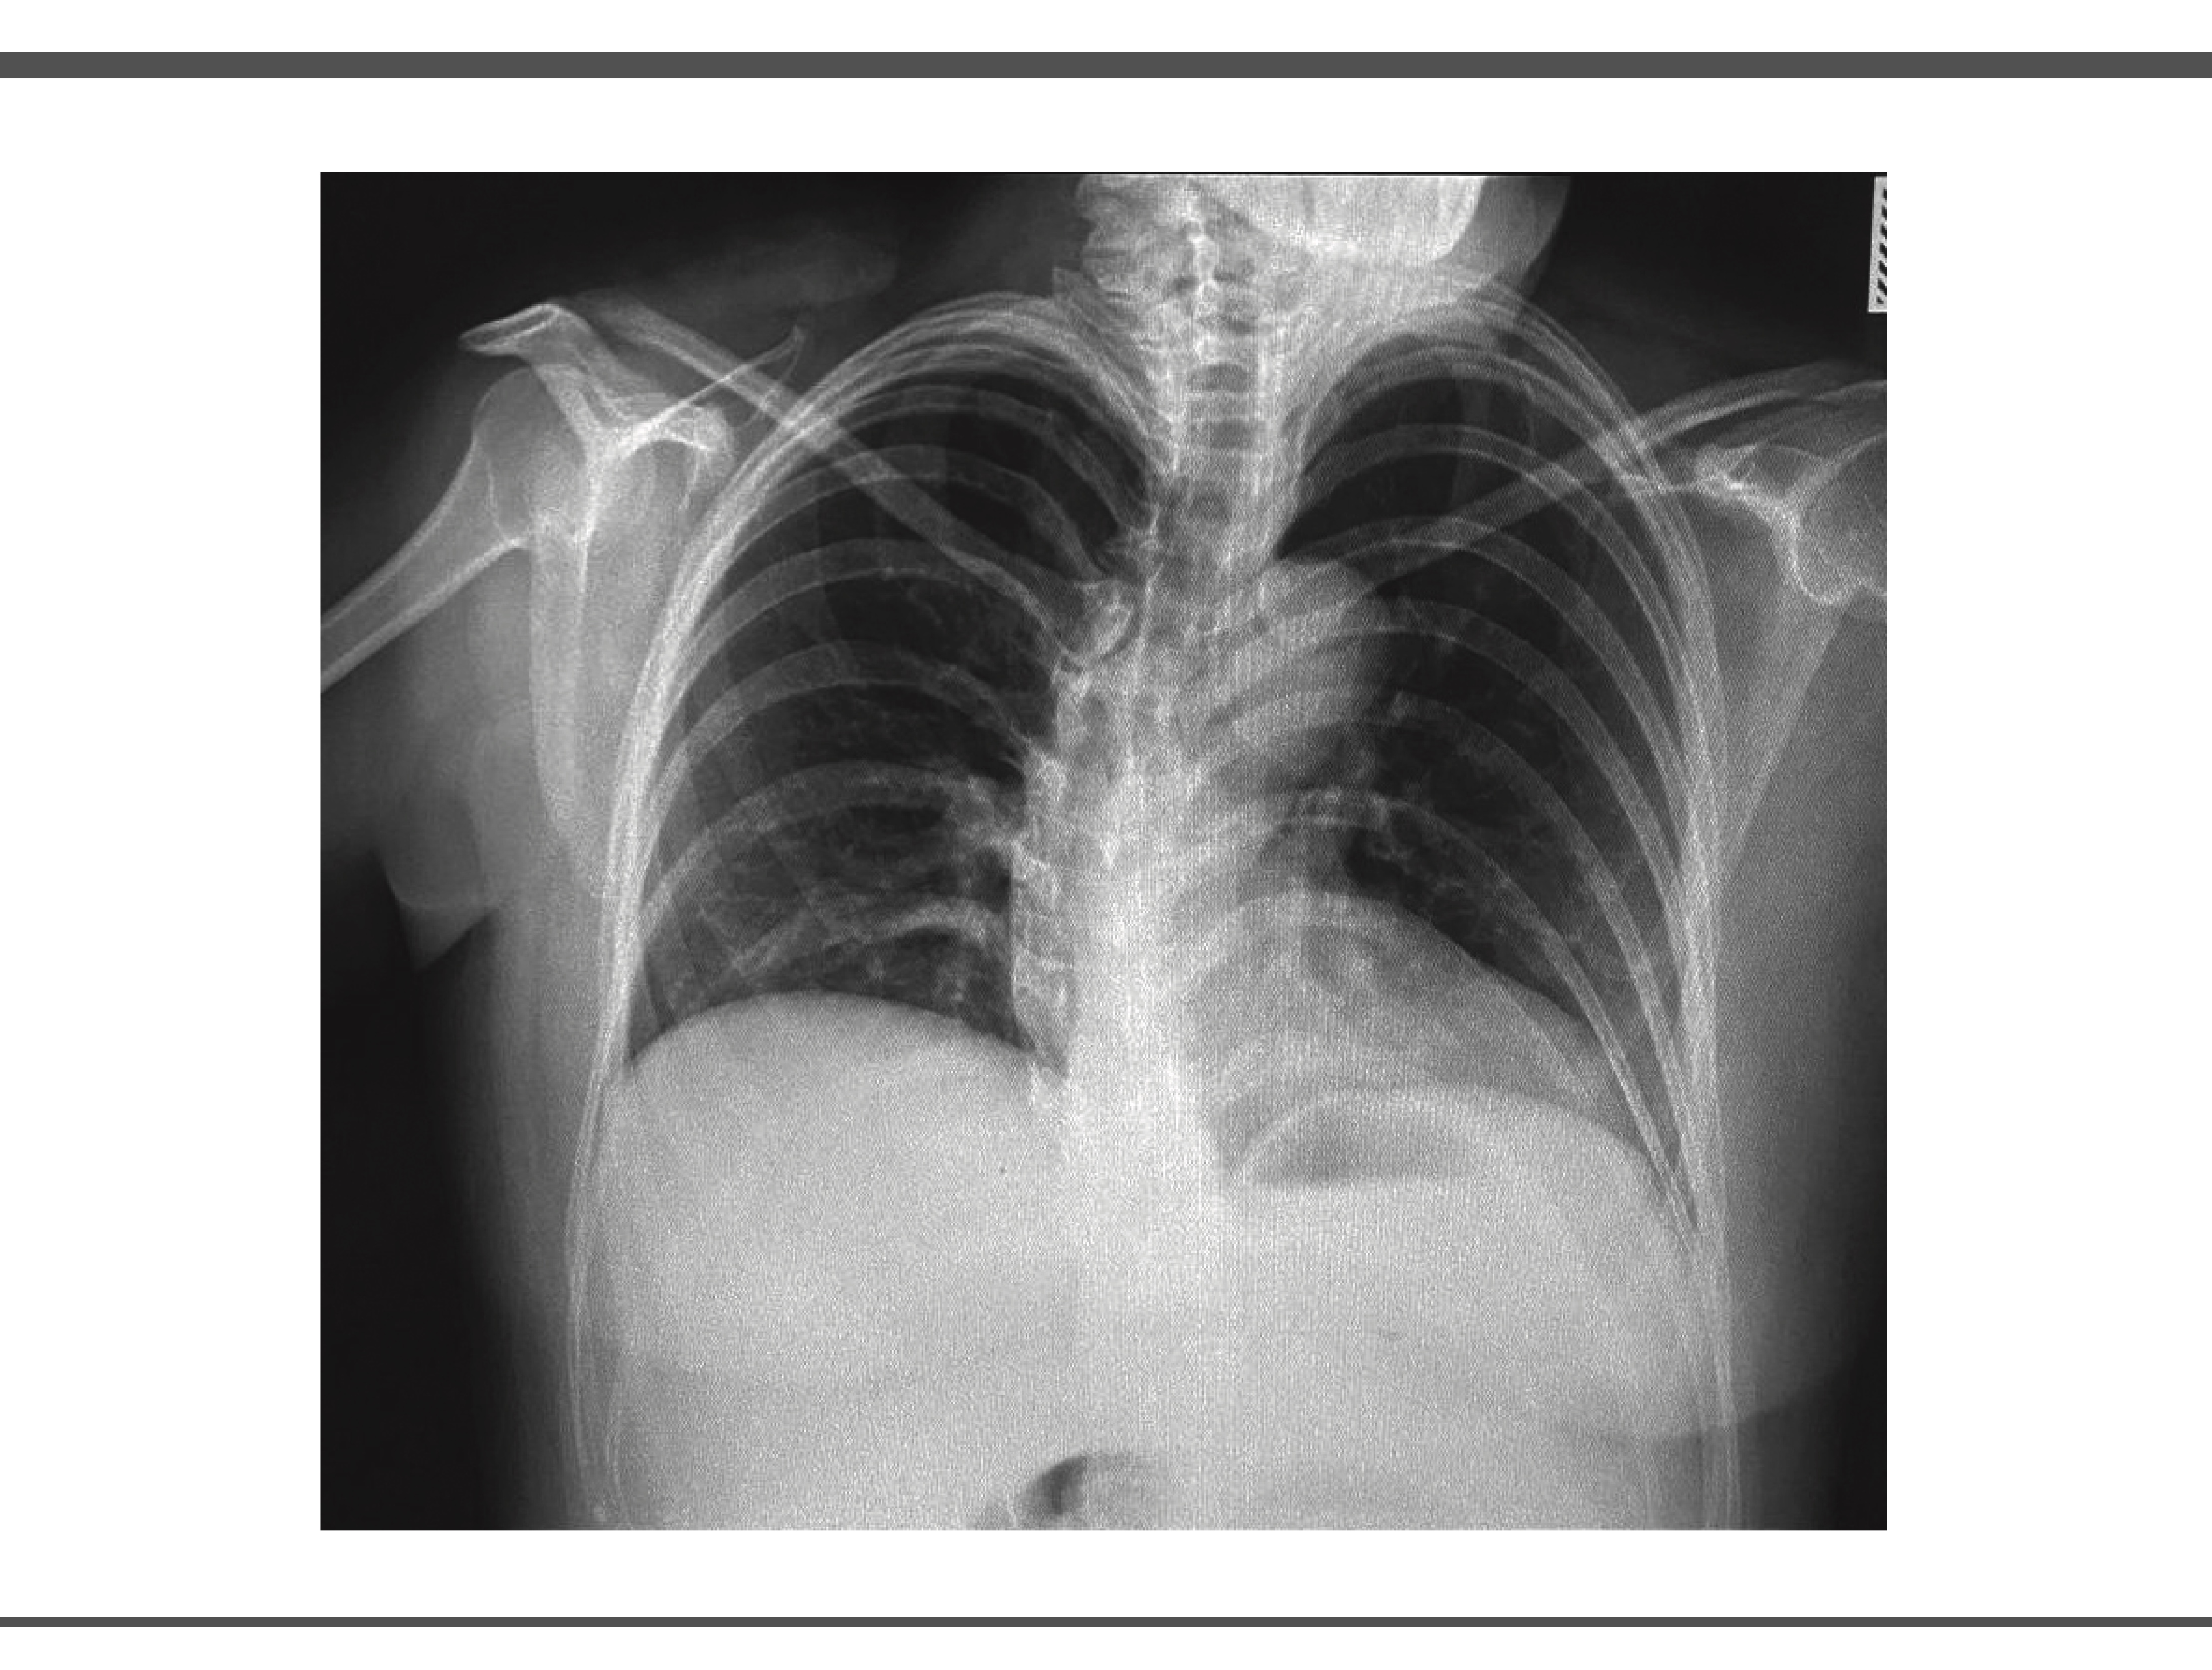

Se realizó electrocardiograma de 12 derivaciones en donde se observa un ritmo sinusal con frecuencia de 81 latidos por minuto, con eje positivo a la derecha con ondas 2 mV T negativas en V1 y V2, sin alteraciones en la conducción ni bloqueos de rama, así mismo se realiza una radiografía de tórax posteroanterior con rotación a la izquierda, en las estructuras óseas se observa desviación dextroconvexa de la columna dorsal y botón aórtico aparentemente aumentado de tamaño, campos pulmonares con adecuada radiopacidad, sin infiltraciones ni ocupaciones anormales ni engrosamientos pleurales, sin presencia de neumotórax (motivo de referencia), (Imagen 1).

IMAGEN 1.

Fuente: expediente del paciente. Fecha Marzo 2025